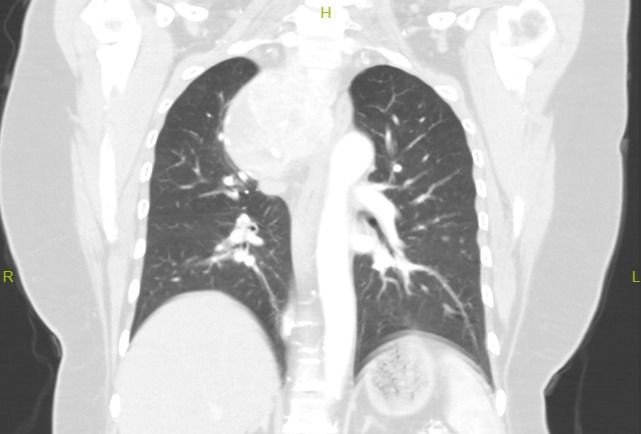

Boyunda kitlesi nedeniyle nefes darlığı ve yutma güçlüğü şikayetleriyle hastanelere başvuran hasta, riskli ameliyat nedeni ile Fethi Sekin Şehir Hastanesi Genel Cerrahi Polikliniği'ne yönlendirildi. Yıllar önce guatr hastalığına bağlı tiroid ameliyatı geçirdiği öğrenilen hastanın yapılan tetkiklerinde, guatr hastalığının nüks ettiği ve 8 x 12 santimetrelik nüks guatr kitlesinin boyundan göğüs kafesine doğru uzandığı görüldü. Nüks guatr kitlesinin solunum yollarına, ana damarlarına ve yemek borusuna baskı yaptığı saptandı.